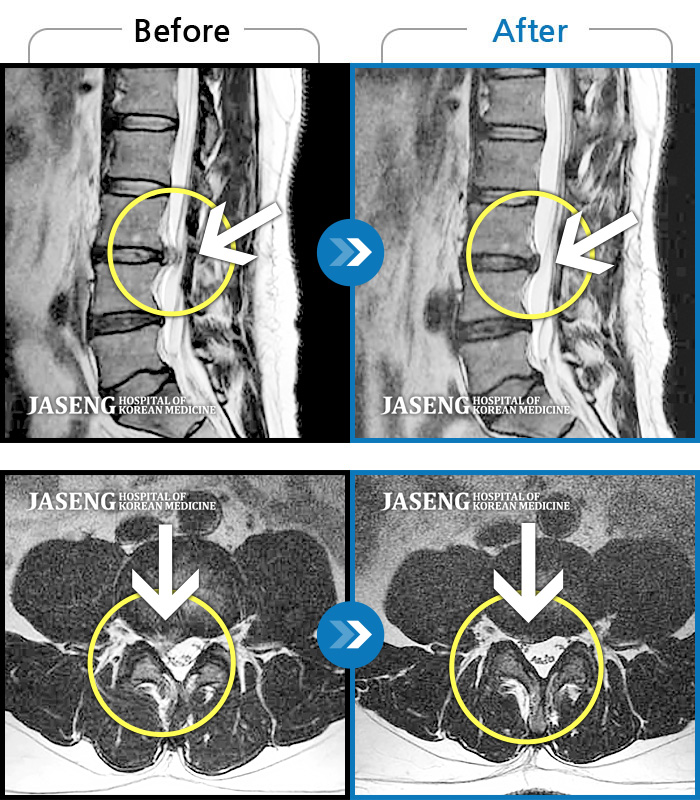

허리디스크

잠실 · 한상욱 원장

허리통증과 함께 좌측 엉치, 허벅지, 종아리 후면으로 저림이 심하여 걷기가 힘들어요.

촬영시기

2021.09.14 ~ 2022.05.14

2022.05.24